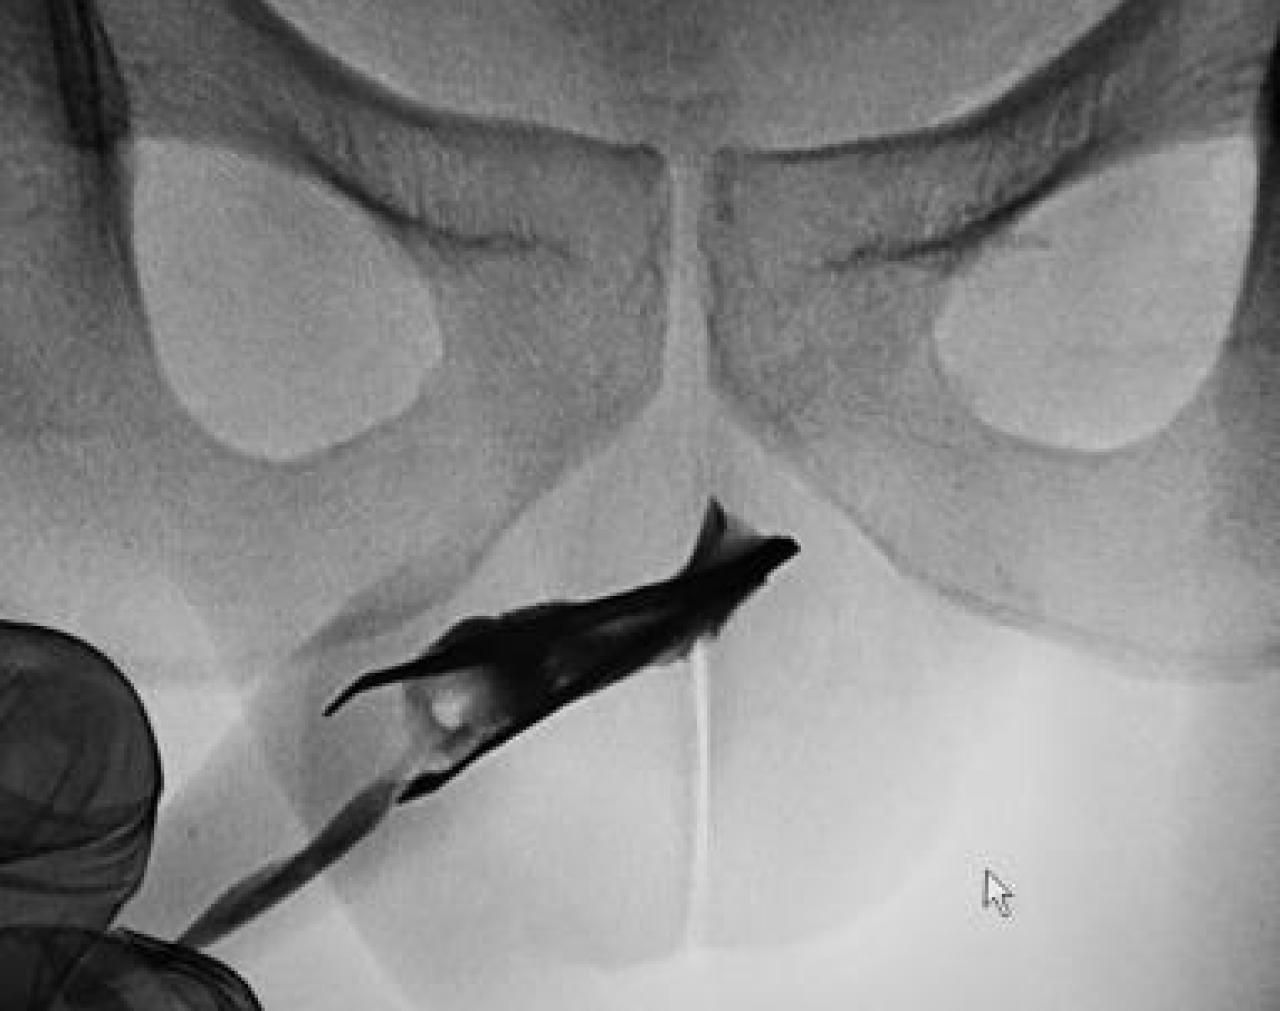

Nur auf den ersten Blick ist dies ein gewöhnliches Röntgenbild. Denn es zeigt eine Pinzette, die in der Harnröhre eines 22-Jährigen steckt. Der hatte den Greifer vier Jahre zuvor dort selbst hineingeschoben.

Bild: M. Abouelazayem/Urology Case Reports